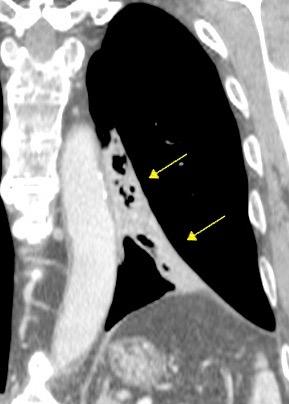

Líneas paraespinales formando un “paréntesis” por encima del diafragma. El signo señala el origen “intratorácico” de la lesión.

Conrad A et al. Pott’s disease associated with large and multiple abscesses in a 30-year-old migrant from Chad. BMJ Case Rep 2018

(lesiones toracoabdominales) La divergencia de las líneas paraespinales apunta a lesión toracoabdominal, que desde el tórax desciende y penetra en el abdomen.

Signo del “iceberg” positivo en Tb vertebral

Afectación por vía hematógena. Región dorsolumbar más frecuente. Afectación inicial: irregularidad de los platillos vertebrales, disminución del disco intervertebral con esclerosis ósea adyacente. Kim. Radiographics.2001